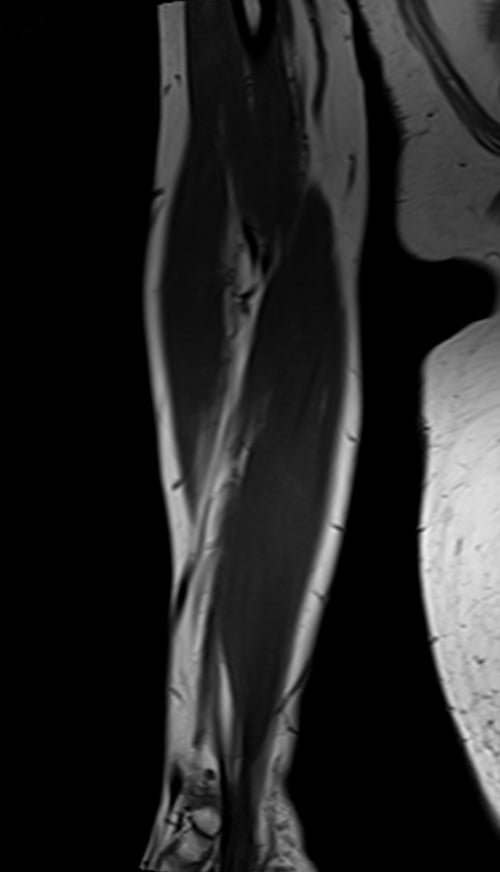

mri fore arm coronal t1 image 2 - MRI